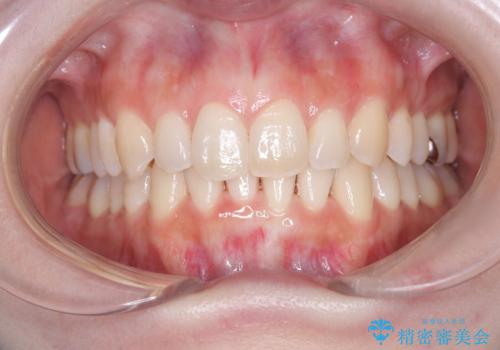

インビザラインで整えた前歯の歯並び

- 患者様は、上下前歯の歯列不正(ガタガタ)を主訴としてご来院されました。治療計画として、透明なマウスピース型矯正装置「インビザライン」を使用し、約2年の期間を見込んで前歯部の歯列を整える方針を立てました。特に下顎前歯に歯肉退縮のリスクがあるため、治療中にIPR(インタープロキシマルリダクション)を行い、歯間を適切に削ることで、過度な圧力を避け、歯肉退縮を防ぎながら配列を進めました。治療は慎重に進め、最終的にきれいで整った前歯の歯並びを目指しました。

インビザラインによる矯正治療は、患者様自身が装着するマウスピース型の装置を使用するため、装着時間の徹底が重要です。特に、下顎前歯の歯肉退縮を避けるため、IPRを施すことで歯間スペースを確保し、歯肉にかかる負担を減らしました。この方法により、歯並びを整えながらも歯肉の健康を保つことができます。治療期間中は定期的にチェックを行い、歯肉の状態や歯の動きを慎重に確認しました。また、治療後はリテーナーを装着して歯並びを維持し、安定させました。